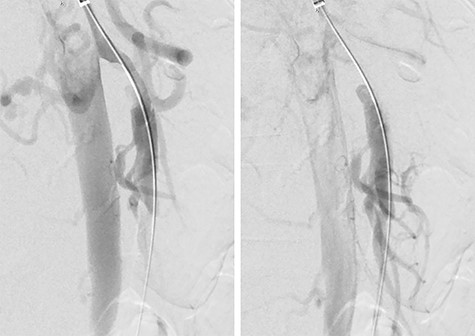

She was admitted and maintained on bowel rest and heparin infusion. Given persistent pain after 2 days of non-operative management, an abdominal arteriogram was performed through a left axillary artery cutdown. The dissection was identified 1.5 cm distal to the origin of the SMA (Fig. 2). Intravascular ultrasound was used to determine diameters and landing zones for stent placement (Fig. 3). The dissection was initially treated with a 6 mm × 40 mm self-expanding stent followed by post-dilation with 4 mm × 40 mm and 6 mm × 40 mm balloons. A 5 mm × 19 mm stent graft was deployed proximally with small overlap and ~3-mm extension into the aorta. Completion angiogram showed <10% residual stenosis (Fig. 4). As the right external iliac artery dissection was small and asymptomatic, no intervention was performed.

Pre-stenting angiogram of the SMA demonstrating early filling of the false lumen including the middle colic artery.